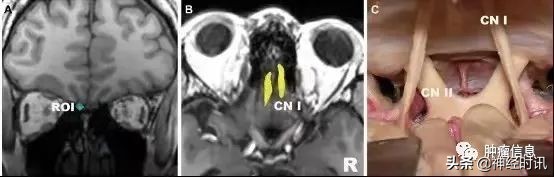

嗅神经

嗅神经连端脑,

属于感觉性神经,

经筛孔进出颅腔,

分布在鼻腔嗅粘膜,

损伤后表现为:嗅觉障碍。

上图 :嗅神经。

A,感兴趣区选在冠状位嗅神经束;

B,高分辨率示踪嗅神经;

C,对应的解剖示意图